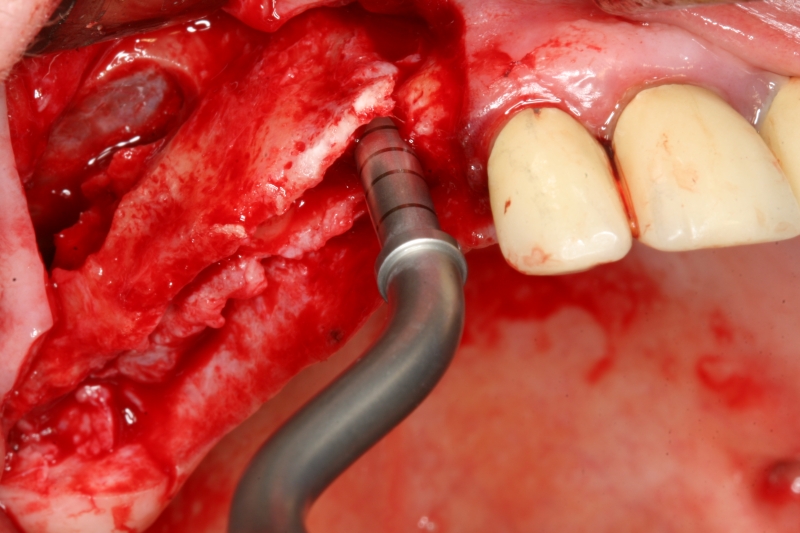

Surgical presentation of the alveolar ridge with reduced amount of horizontal bone available